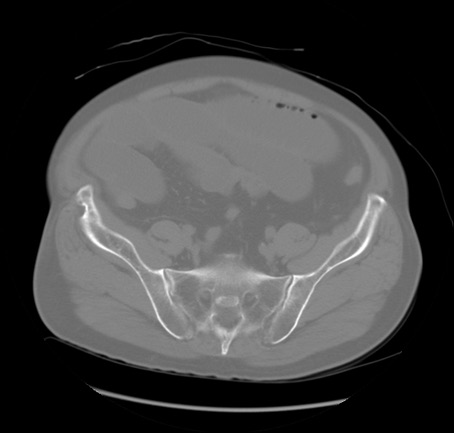

冠状断像

【症例】 60歳代男性

【主訴】 腹部膨満、嘔吐

【現病歴】5日前頃より倦怠感を認め食事量減少し4日前の朝嘔吐、食事摂取困難となった。 3日前近医受診し点滴施行され整腸剤などを処方された。 当日他院を受診し、腹部膨満著明、炎症反応の上昇(CRP10.8、WBC11200)あり、紹介受診となる。

【身体所見】 意識JCS1 受け答えがはっきりしないBP 111/57mHg、 P 67bpm、、BT35.2°C、SpO2 97%(RA)、 腹部:膨隆、打診で鼓音あり、全体的に圧痛有り、腸蠕動音(-)、反跳痛ははっきりせず。

【データ】WBC 11400、CRP 14.20